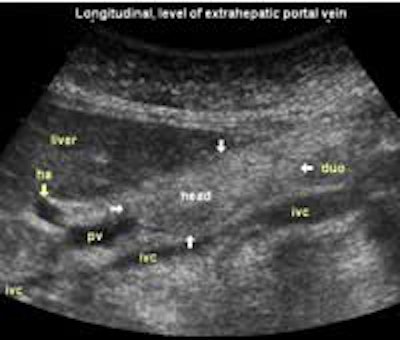

Longitudinal planes from right to left:

![]() Image21 |